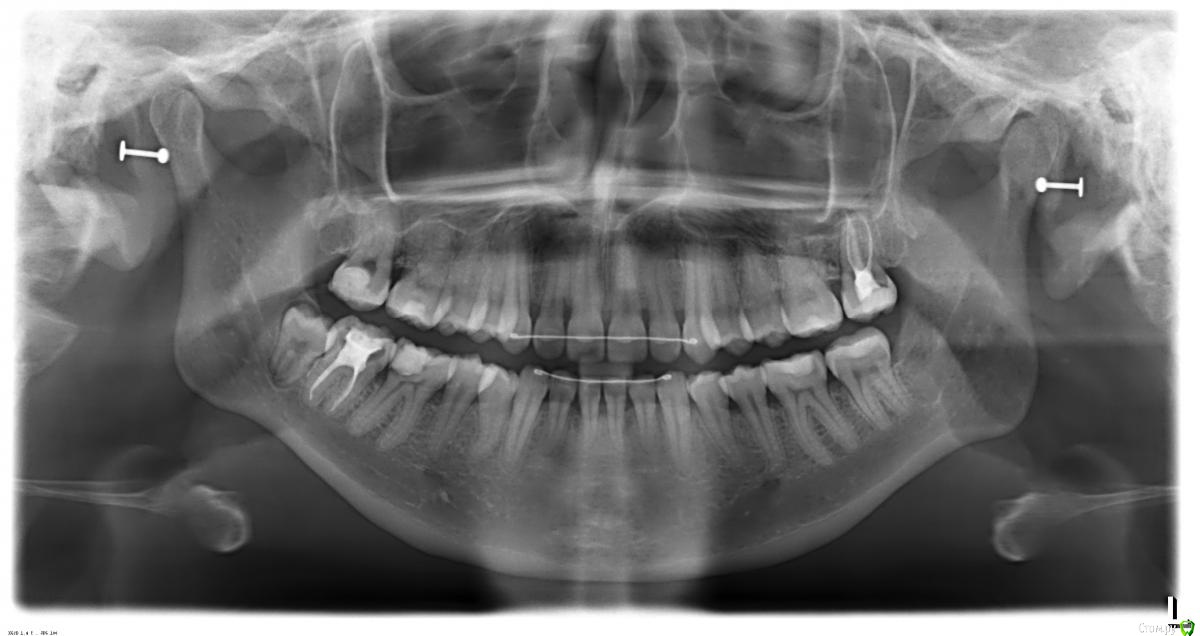

IshIm0 Опубликовано 1 апреля, 2016 Поделиться Опубликовано 1 апреля, 2016 Добрый день коллеги. Девочке 24 года, 1.5 года после ортодонтического лечения, пол года назад заметила рецессию. Как я думаю: 1 этап - вестибулопластика. 2 этап - через пол года забор сст с неба и устранение рецессии. Восьмерку кстати тоже удалять нужно. Поделитесь своим ви'дением этой ситуации, советами, "подводными камнями" ) Все ли верно по срокам? Ссылка на комментарий

Доктор Добрых Дел Опубликовано 2 апреля, 2016 Поделиться Опубликовано 2 апреля, 2016 В чем причина данной рецессии? отсутствие вестибулярной кости. Ссылка на комментарий

zzkz Опубликовано 6 апреля, 2016 Поделиться Опубликовано 6 апреля, 2016 отсутствие вестибулярной кости.Её может не было изначально. Ортодонтия спровоцировала. Тож за латеральный лоскут Ссылка на комментарий